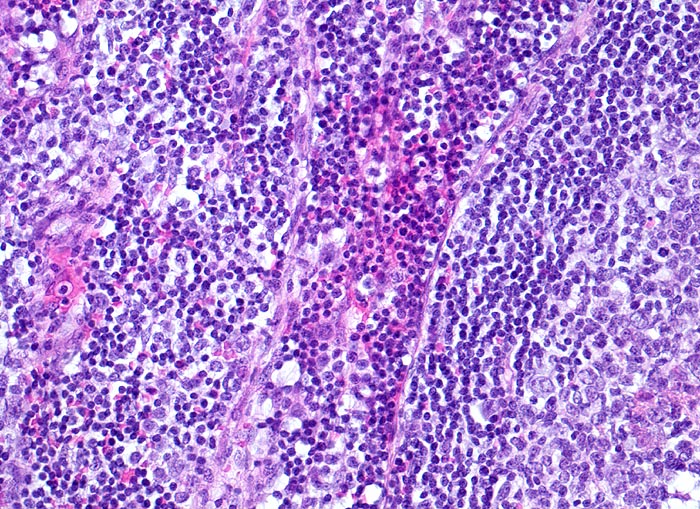

In der mittleren Dermis bilden sich Nekroseareale, welche von palisadierenden Histiozyten, mehrkernigen Riesenzellen und eosinophilen Granulozyten demarkiert werden. Die regionären Lymphknoten zeigen ebenfalls eine retikulozytär abszedierende Entzündung. Diese ist jedoch nicht spezifisch. Sie kommt auch vor bei Yersiniose, atypischer Mykobakteriose, Sporotrichose, Tularämie, Tumoren, Lymphogranuloma venereum und Coccidiomykose.